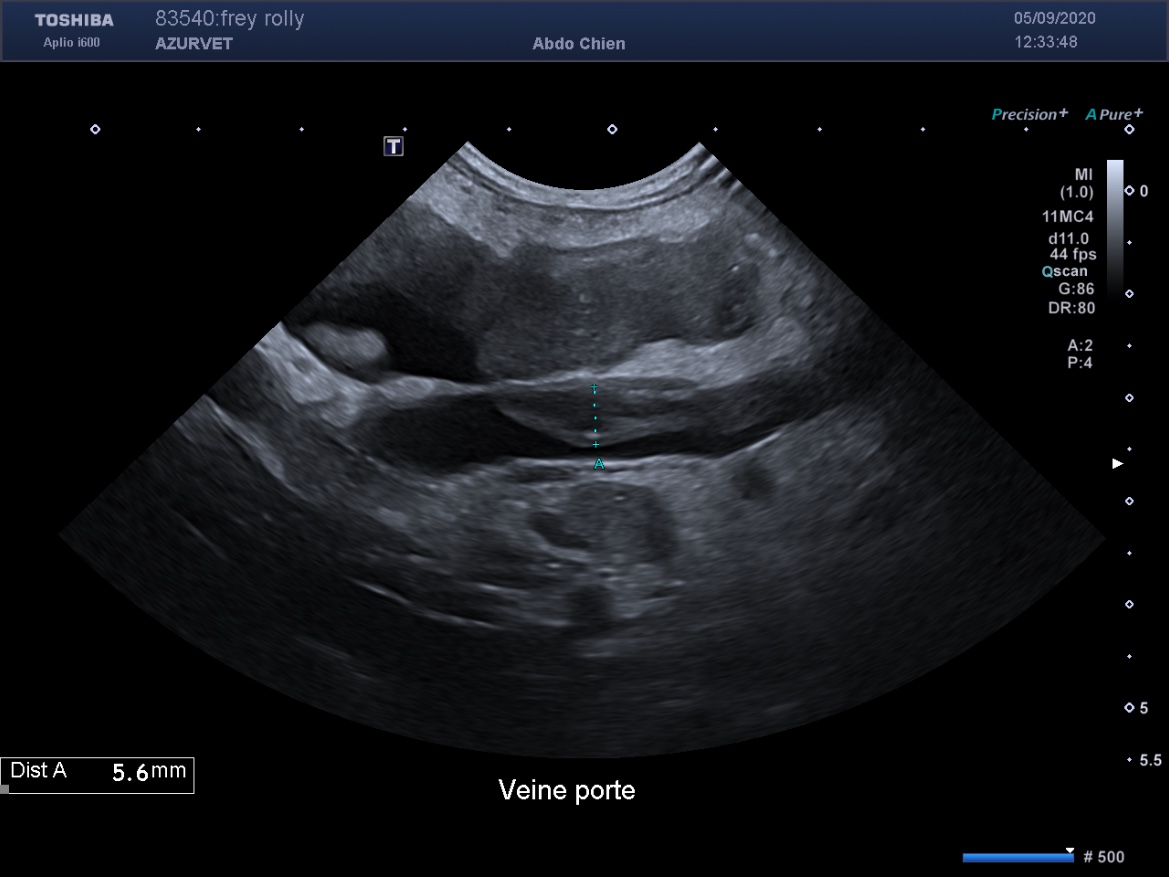

3) la recherche de thrombus artériel ou veineux (secondaire à la fuite de protéines anticoagulantes dans le tube digestif) : figure 4 et 5 ci dessous.

Figure 5 : thrombus porte sub occlusif chez un bouledogue français souffrant de lymphangiectasie.